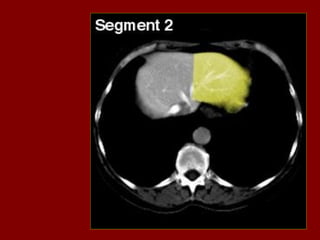

INCISÃO SOBRA A VEIA HEPÁTICA DIREITA

INCISÃO SOBRA AVEIA HEPÁTICA DIREITA